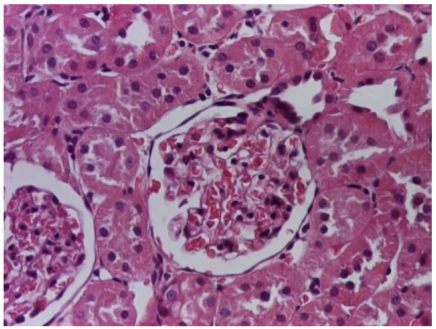

Table 4 below presents histological proof for renal damage in the G-IV group suffering from a dual metabolic impairment, albeit treated with statin.

Table 4.

Histological proof for renal damage in the diabetic-and-obese statin-treated group G-IV.

The histological extent of lesions suggests a definite inflammatory process in the renal matrix and glomeruli, but the extent of the disruptive process as resulting from an average nephron pool loss is limited. This is consistent with the limited duration of our experiment, with definite development of chronic kidney disease taking sometimes as long as 24 weeks. However, expecting this limited extent of damage, we chose a relatively short—proportionate—duration of statin treatment. Our results demonstrate a statistically significant higher retention of creatinine and urea in plasma—a reflection of the respective reduction in renal function—in every single experimental group (G-II to G-IV) in comparison to the control group G-I. The diabetic group G-III demonstrates the highest values for both creatinine and urea across the whole experiment population. The plasma concentrations of retention byproducts in both G-II and G-III are statistically significantly higher compared to the control G-I, indicating that each condition independently leads to important impairment in kidney function. The assumption of concurring actions in a model exhibiting obesity and diabetes simultaneously should translate into outcomes—renal and inflammatory—with values skewed from normality, the dimension of departure from the normal range at least as big as in any of the models exhibiting an individual condition.